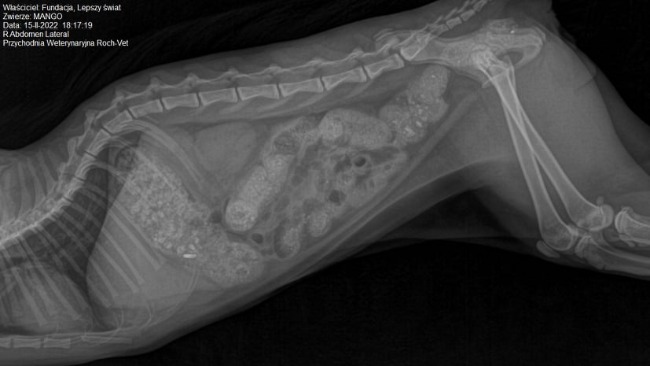

Tydzień temu Mango posmutniał, zaczął gorączkować i odmawiać jedzenia, pojawiły się trzecie powieki i powiększone węzły chłonne pod żuchwą oraz wyciek z oczu. Został więc wprowadzony antybiotyk i odpowiednie leczenie. W weekend Mango z niewiadomych przyczyn zaczął jeść żwirek z kuwety i wymiotować nim. Dostał leki na nudności i zobojętniające kwas żołądkowy, ponieważ było podejrzenie, że robi to z powodu nudności, aby oczyścić żołądek. We wtorek (15.02) Mango się „zatkał”, nie umiał się wypróżnić a kał utknął mu w odbycie. Pojawiła się krew i w trybie pilnym wylądował z powrotem u weterynarza. Zdjęcie rentgenowskie wykazało duże masy żwirku zalegające w jelicie, zadecydowano o hospitalizacji i zastosowaniu lewatywy. Już przy próbie założenia wenflonu weterynarze zauważyli, że coś jest nie tak, bo jego żyły są bardzo cienkie i pękają, a co za tym idzie, założenie wkłucia dożylnego i podanie kroplówki okazało się niemożliwe. Następnego dnia pojawiła się wysoka, 40 stopniowa, trudna do zbicia gorączka. Mimo pękających naczyń krwionośnych, na kilka razy udało się pobrać krew do badań. Z morfologii wyszła anemia i żółtaczka hemolityczna... Jeszcze czekamy na wyniki biochemii. Weterynarz powiedziała, że nie znają przyczyny, ale jego organizm niszczy własne erytrocyty i płytki. Będą wprowadzać sterydy. Koszty jego leczenia przerosły moje możliwości, dlatego proszę Was o pomoc. Szacowany koszt jego leczenia i hospitalizacji to na ten moment 1017zł, a każda kolejna doba pobytu, leczenia i kroplówek to ok 150 zł.